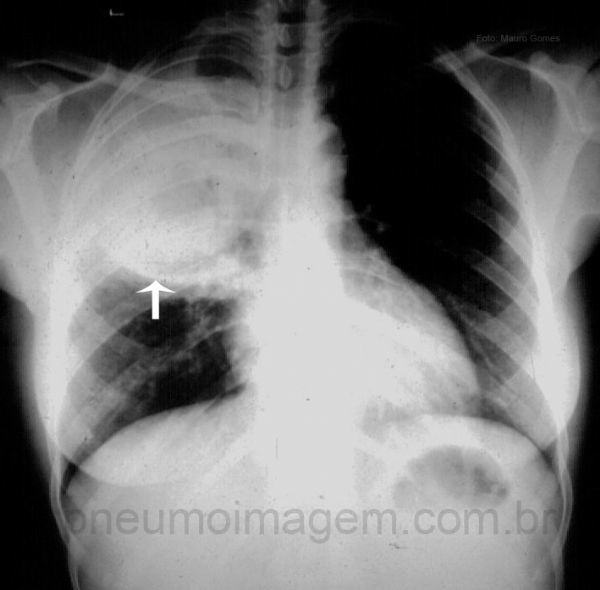

Rx: derrame pleural, pneumonia redonda “pseudotumoral”, abscesso

Radiografia de tórax:

Rx: broncopneumonia ou lobar

Organismos causadores de pneumonia capazes de evoluir com abscesso (> 2 cm)?

Anaeróbios: doença periodontal, broncoaspiração, alcoolismo, distúrbios deglutição

S. aureus: drogas IV, endocardite, fibrose cistica, neonatos

Klebsiella: etilistas, DM